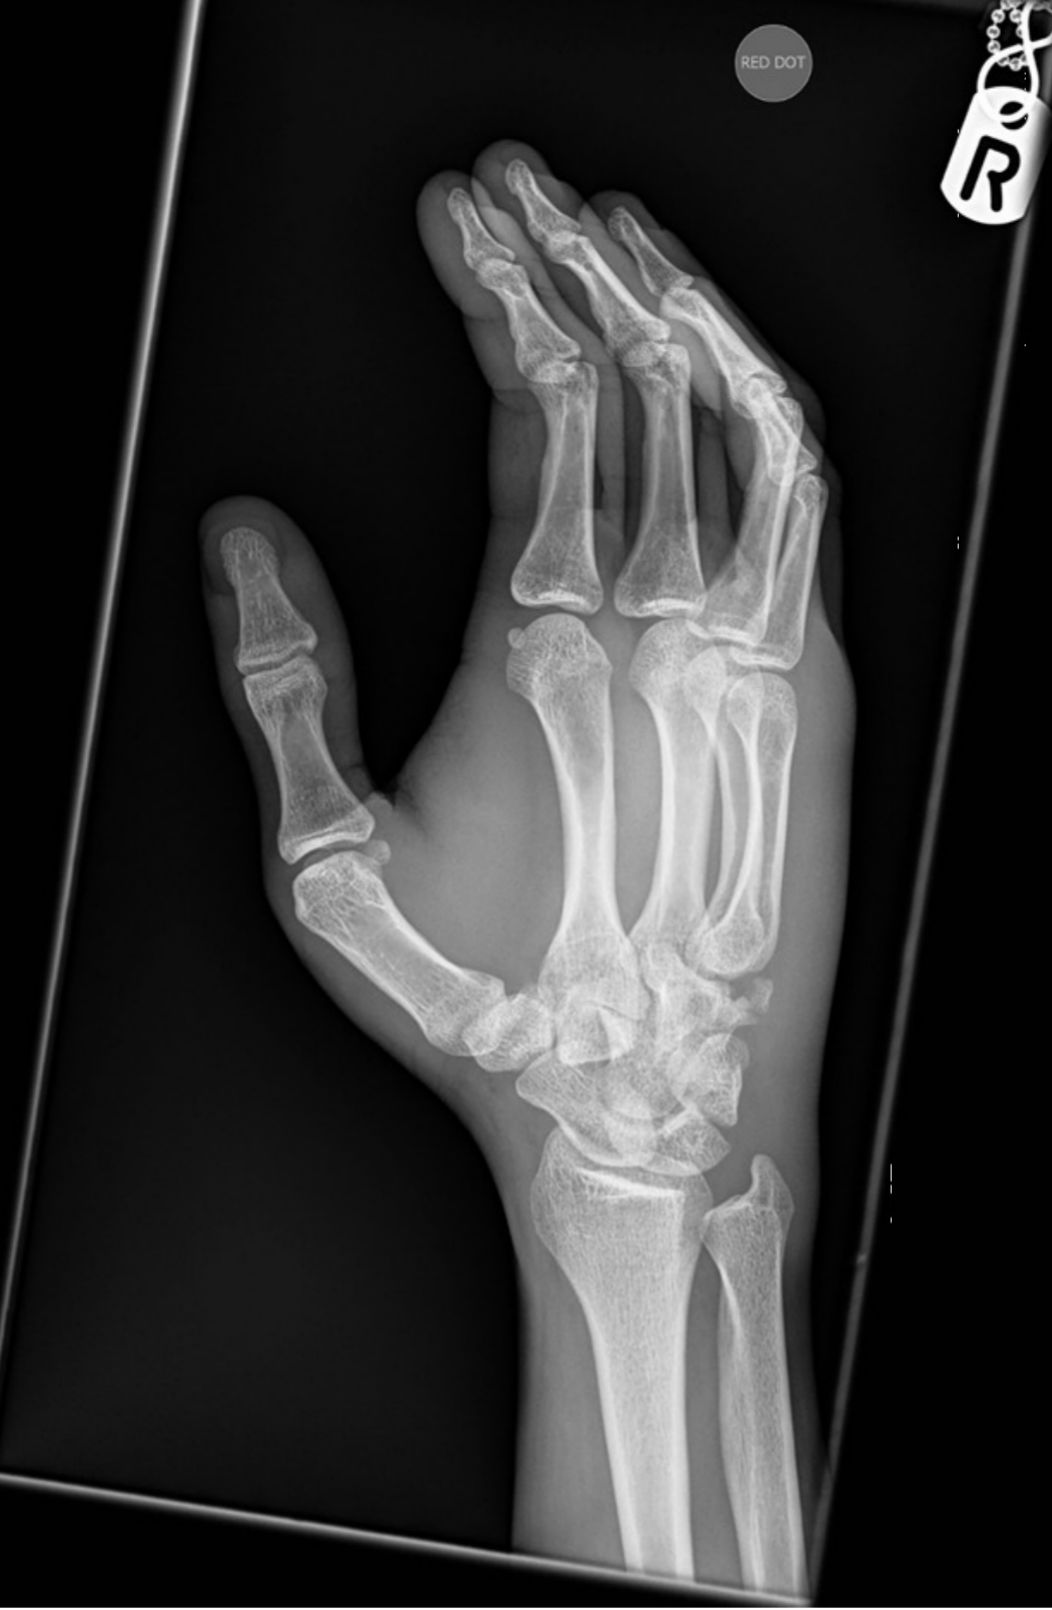

X线检查:正侧位均未发现骨折。因为患者第五掌骨底部与腕掌关节有压痛,故加做侧位片,如下图所示。

把这幅示意图发上来,大家进一步看一看。

右手斜位片,红色箭头提示钩骨骨折。